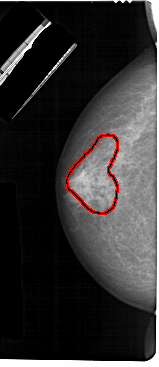

LEFT_CC LINES 5491 PIXELS_PER_LINE 2371 BITS_PER_PIXEL 12 RESOLUTION 43.5 OVERLAY

FILE: A_1302_1.LEFT_CC.OVERLAY

TOTAL_ABNORMALITIES 1

ABNORMALITY 1

LESION_TYPE CALCIFICATION TYPE PUNCTATE-AMORPHOUS DISTRIBUTION REGIONAL

ASSESSMENT 4

SUBTLETY 3

PATHOLOGY BENIGN

TOTAL_OUTLINES 1

BOUNDARY